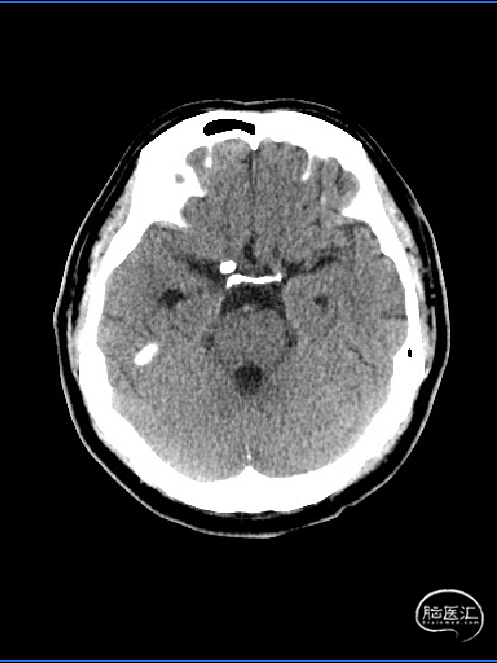

术前CT:

术前影像学检查:外院查颈动脉CTA示:1.右侧颈内动脉C7段前壁宽颈动脉瘤,大小约4mm;2.蛛网膜下腔出血。